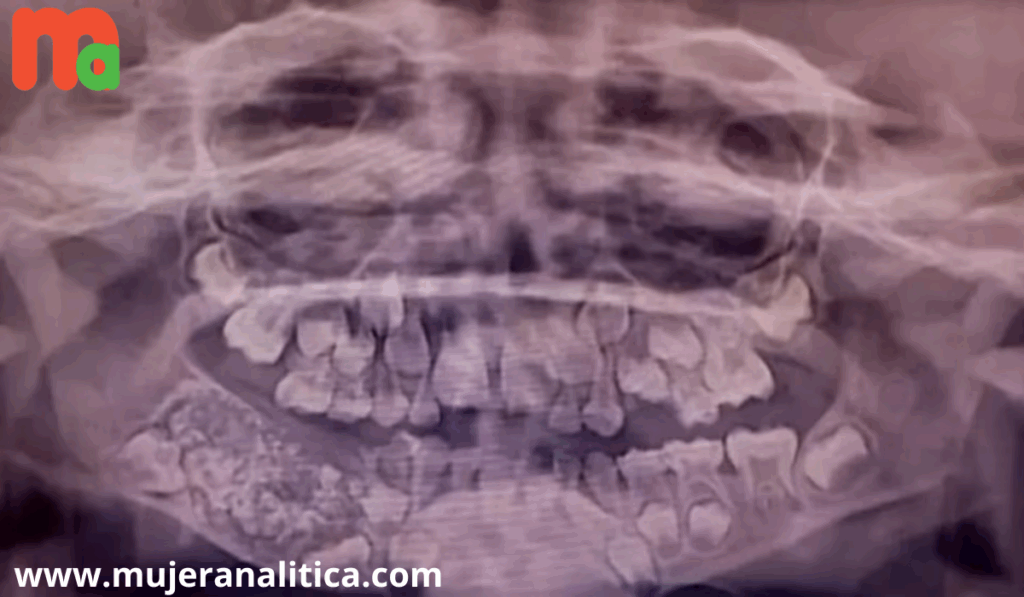

Las radiografías y tomografías computerizadas revelaron la presencia de una masa de aproximadamente 200 gramos alojada en el interior de la mandíbula. El Dr. Senthilnathan, responsable del Departamento de Cirugía Oral y Maxilofacial, identificó la anomalía como un “odontoma compuesto”, una variante benigna de tumor directamente relacionada con el desarrollo dental.

“La especie de tumor que detectamos impidió el crecimiento permanente de los molares en el niño en el lado afectado”, explicó el cirujano tras completar la operación. Las imágenes médicas mostraban numerosos dientes rudimentarios agrupados en un tejido con forma de bolsa, una presentación clínica poco frecuente en la literatura especializada.

La magnitud del descubrimiento sorprendió incluso a los médicos más experimentados. Según informó Science Alert, la bolsa contenía 526 pequeños dientes de dimensiones variables, desde apenas 0,1 milímetros hasta 15 milímetros de longitud. El proceso de clasificación y contabilización de cada pieza dental requirió cinco horas adicionales de trabajo meticuloso en el laboratorio.

La Dra. Pratibha Ramani, directora del Departamento de Patología Oral y Maxilofacial, destacó que todos los dientes extraídos presentaban las estructuras características de las piezas dentales normales: corona, raíz y recubrimiento de esmalte. “Incluso la pieza más pequeña tenía las características de un diente tradicional”, subrayó la especialista, quien enfatizó la ausencia de precedentes con tal número de dientes en los registros médicos mundiales.